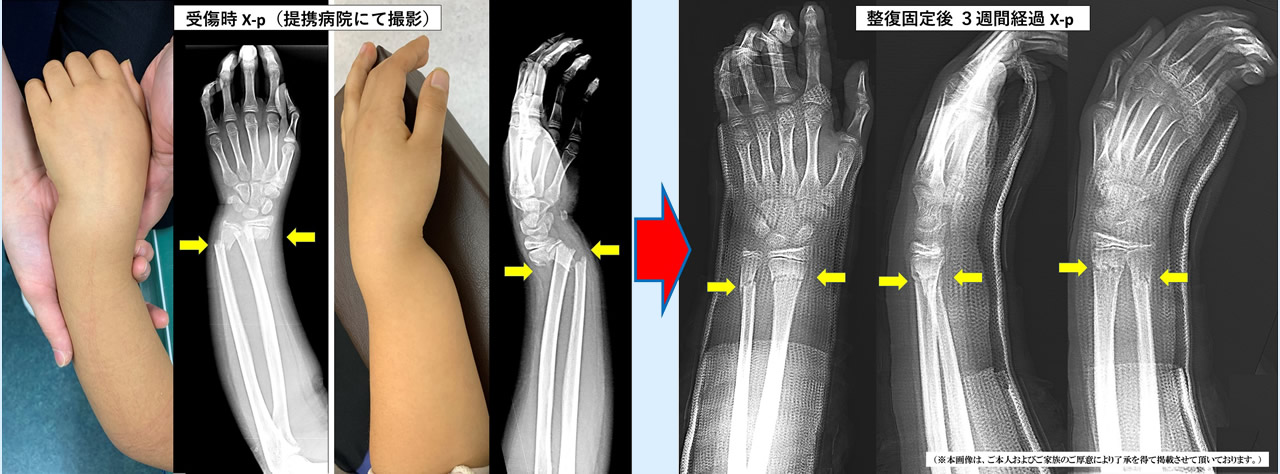

当院ではこのような患者様も徒手整復と固定管理により、手術を回避して、

後遺症なく早期に回復されております。

(※本画像・個人情報につきましては、ご本人およびご家族のご厚意により了承を得て、掲載させて頂いております。)

(9歳女児 左前腕両骨骨折)

9歳女児

左前腕両骨骨折

祝日に自宅で転倒した際に、手をついて負傷された患者様。写真で一目瞭然ですが、手首が骨折して強く変形していました。手術適応である程のひどい骨折でしたが、すぐに当院で処置(徒手整復・固定)を行うことができたため、手術を回避することができました。3週間ギプスで固定後、手首のリハビリを行い、受傷から6週間で完治。

今では後遺症もなく元気に遊んでいるとのことです。